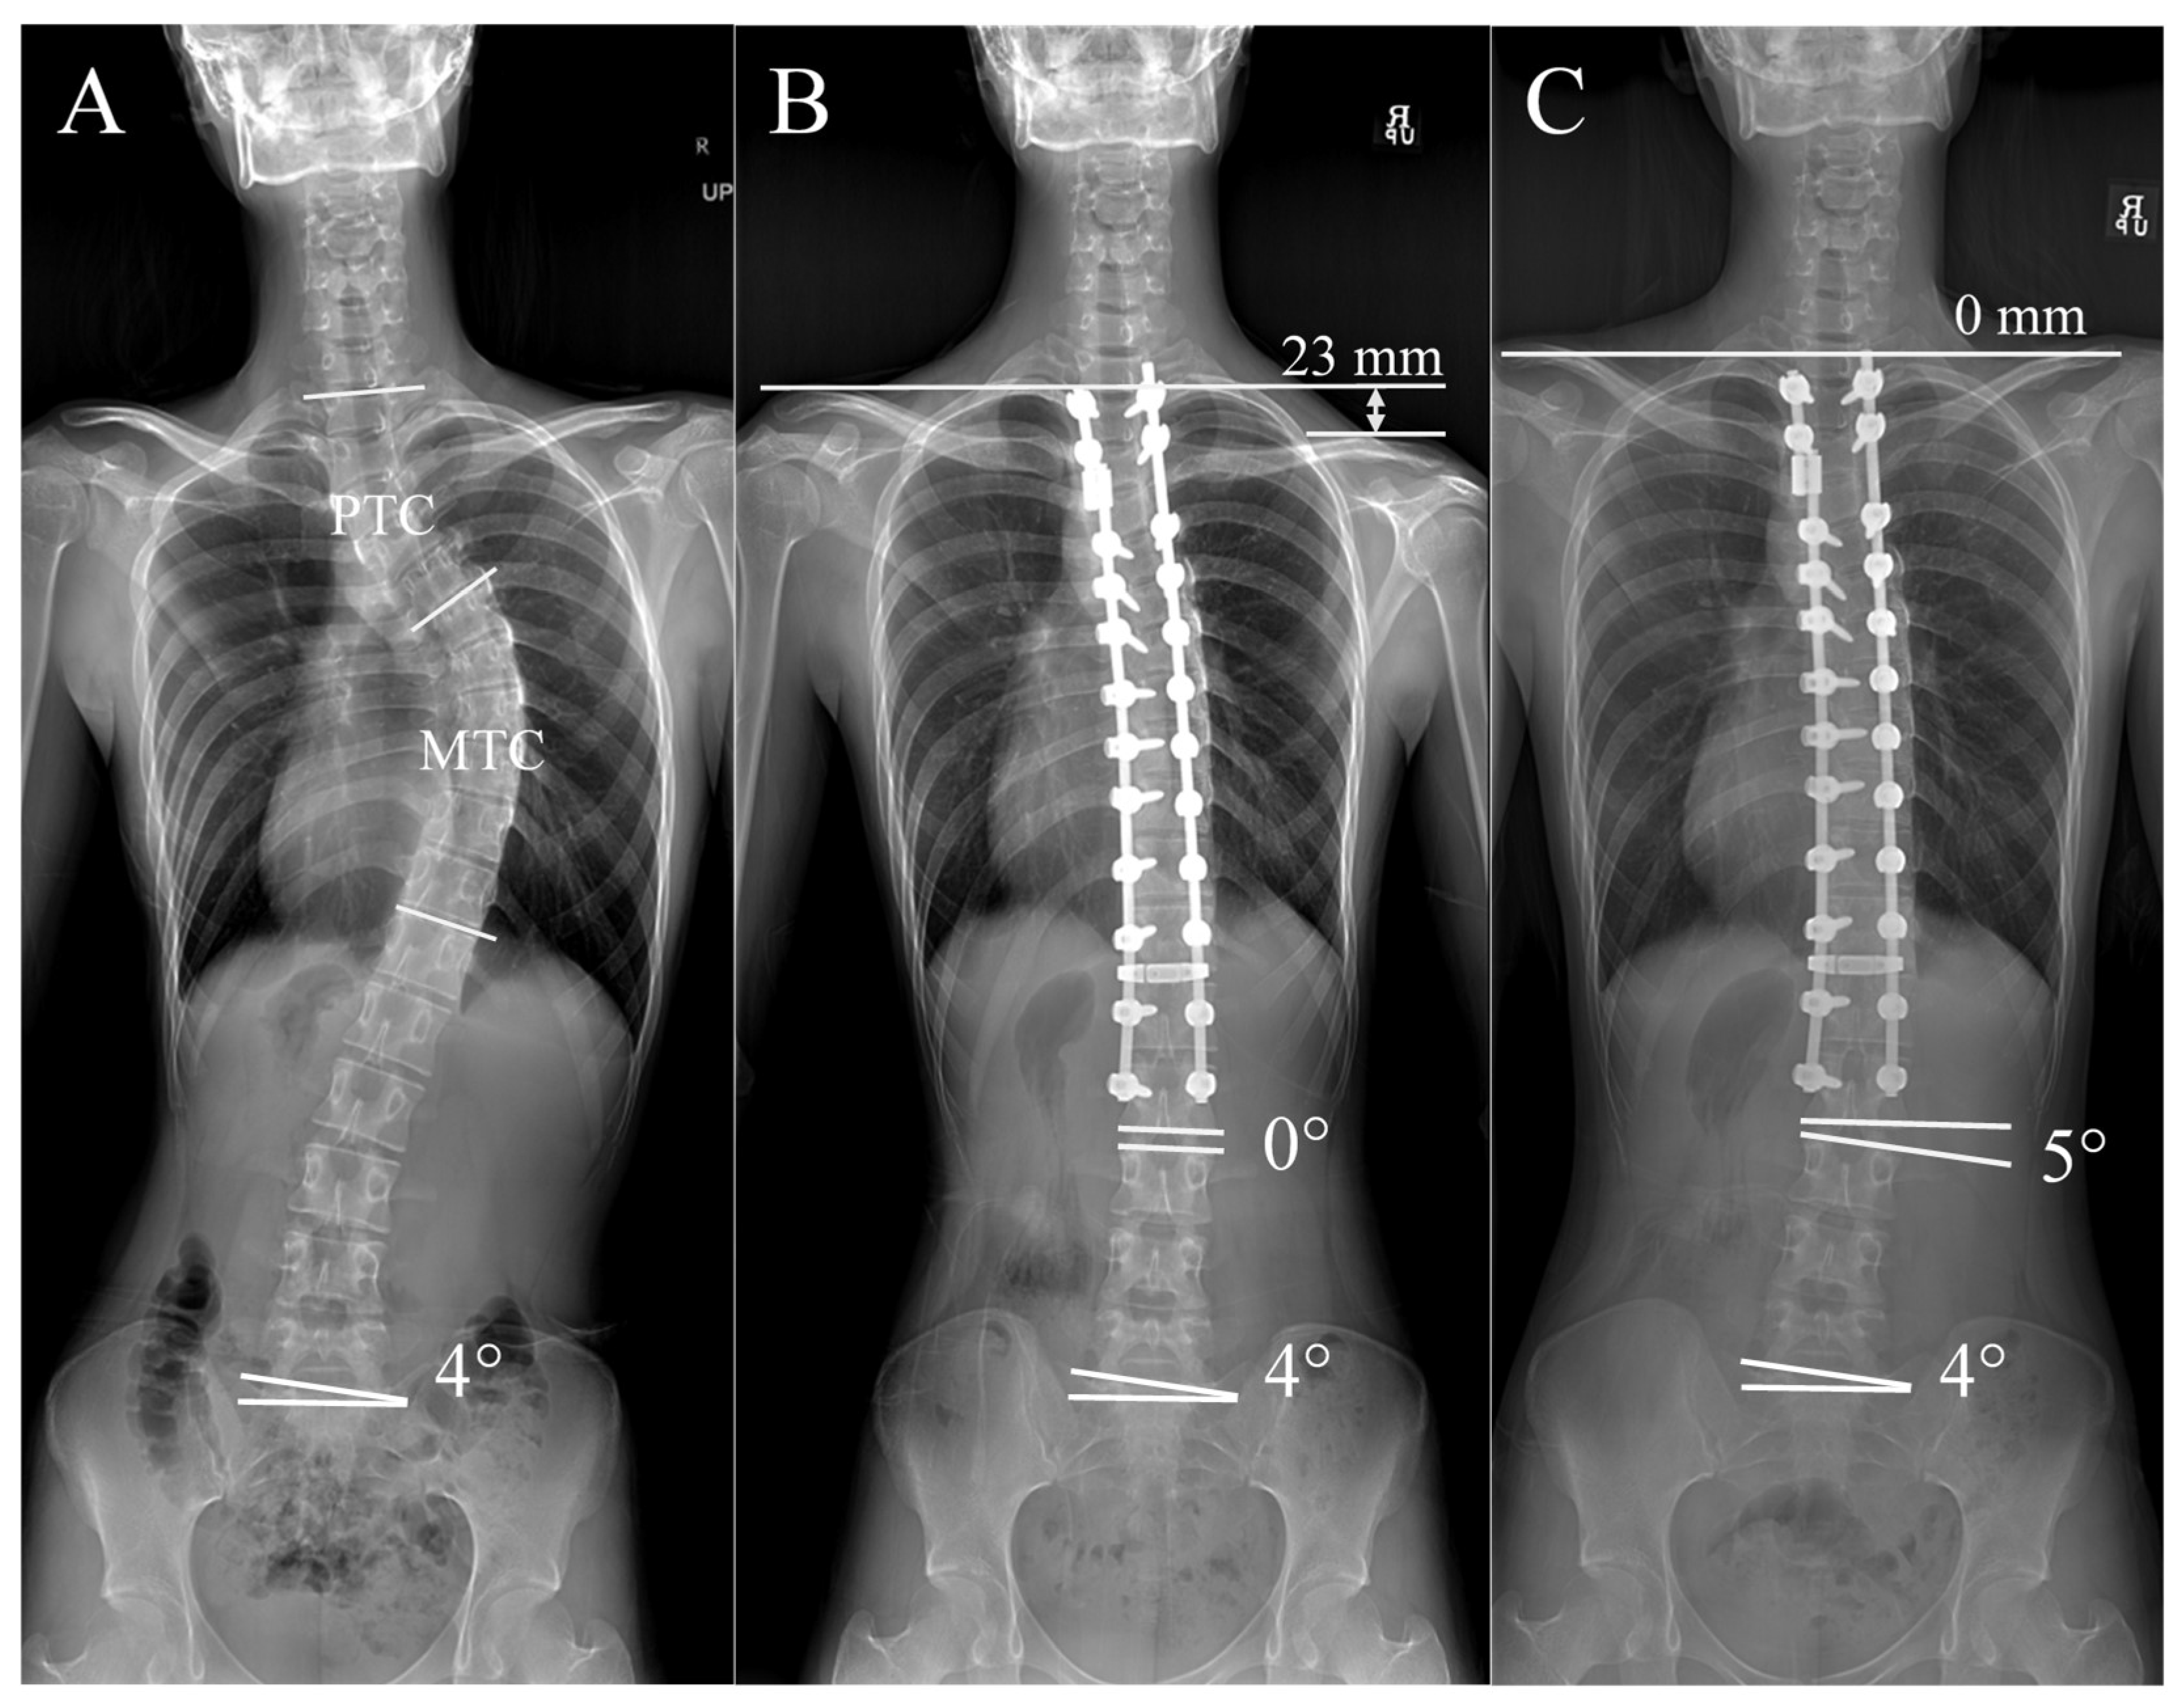

2.2. Demographic and Radiographic Measurements

3.2. Distal Adding-On and Postoperative Shoulder Balance over Time

| DA | Distal Adding-on |

| DWA | Distal Wedge Angle |

| RSH | Radiologic Shoulder Height |

| PTC | Proximal Thoracic Curve |

| MTC | Main Thoracic Curve |

| DA Occurrence | 20 (47.6%) | 13 (28.9%) | 6 (18.2%) | 0.02 * |

| RSH (mm) | ||||

| Postop immediate | 22.4 ± 2.5 | 21.2 ± 3.1 | 20.6 ± 2.8 | 0.03 * |

| Postop 1 M | 12.9 ± 2.0 | 14.6 ± 2.3 | 15.1 ± 2.4 | 0.04 * |

| Postop 3 M | 10.8 ± 1.8 | 13.2 ± 2.1 | 14.3 ± 2.2 | 0.02 * |

| Postop 6 M | 9.2 ± 2.3 | 11.7 ± 2.5 | 12.9 ± 2.6 | <0.01 * |

| Postop 1 Y | 8.7 ± 2.4 | 10.5 ± 2.6 | 11.4 ± 2.8 | <0.01 * |

| Postop 2 Y | 8.0 ± 2.6 | 9.4 ± 2.9 | 10.2 ± 3.0 | <0.01 * |